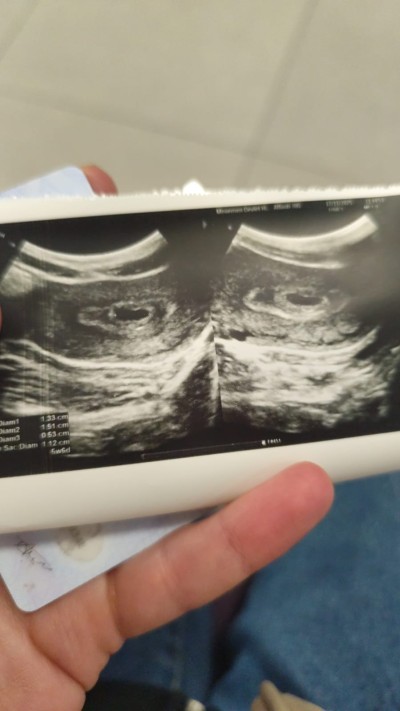

kizlar kese var Bebek yok 6+0 normalmi tekrar kontrole ne zaman gitmeliyim

Gebelik haftası 6